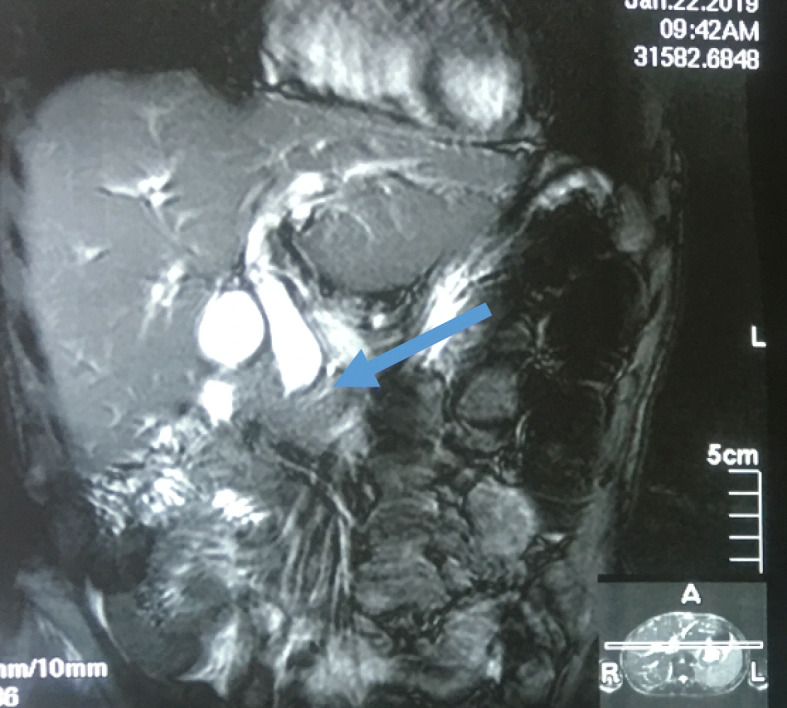

Fig. 3.

Magnetic resonance cholangiopancreatography showing dilated intrahepatic and extrahepatic biliary system down to the distal part (arrow)

Fig. 4.

Magnetic resonance cholangiopancreatography showing dilated intrahepatic and extrahepatic biliary system down to the distal part, where it is obstructed by a mass (arrow)